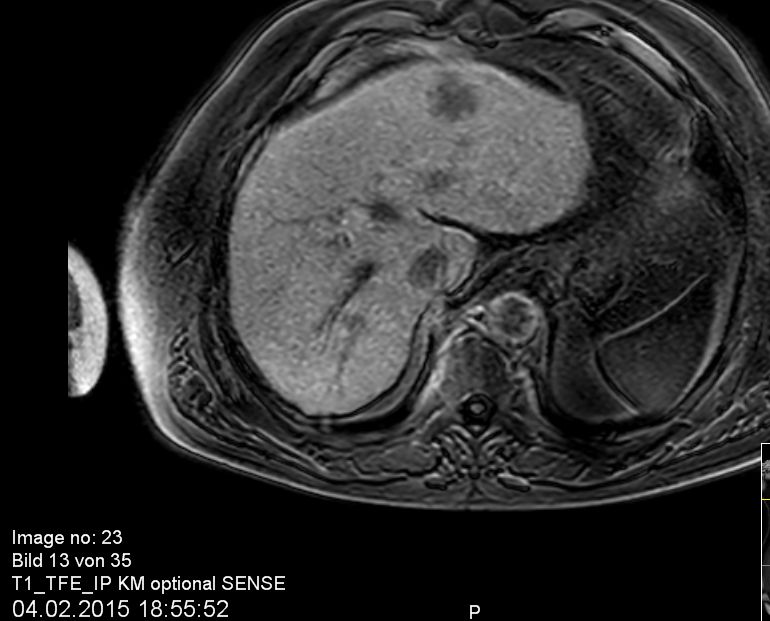

| intrahepatische Filiae | 68-jähriger Mann mit bekannter Leberzirrhose nach Alkoholabusus.

Im CT mehrere hypervaskuläre Herde gesehen.

Im MR beste Darstellung auf den Spätaufnahmen nach leberspezifischem Kontrastmittel in der hepatobiliären Ausscheidung.

Unterhalb der Zwerchfellkuppel links subkapsulär ventral gelegener Herd im 2. Segment 34 mm.

In der koronaren Schichtung im 8.Lebersegment ein 8,5 mm kleiner signalabgesenkter Leberherd.![]() |